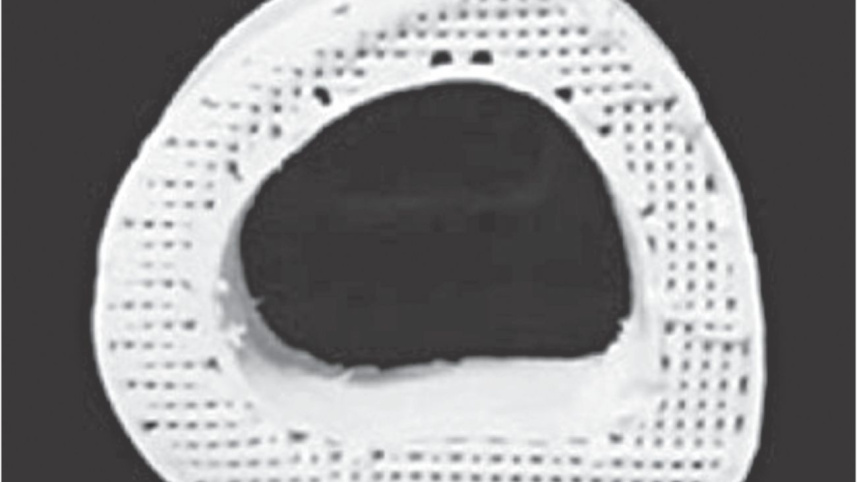

A Northwestern Engineering research team has developed a 3-D printable ink that produces a synthetic bone implant that rapidly induces bone regeneration and growth. This hyperelastic "bone" material, whose shape can be easily customised, one day could be especially useful for the treatment of bone defects in children.

Bone implantation surgery is never an easy process, but it is particularly painful and complicated for children. With both adults and children, often times bone is harvested from elsewhere in the body to replace the missing bone, which can lead to other complications and pain. Metallic implants are sometimes used, but this is not a permanent fix for growing children.